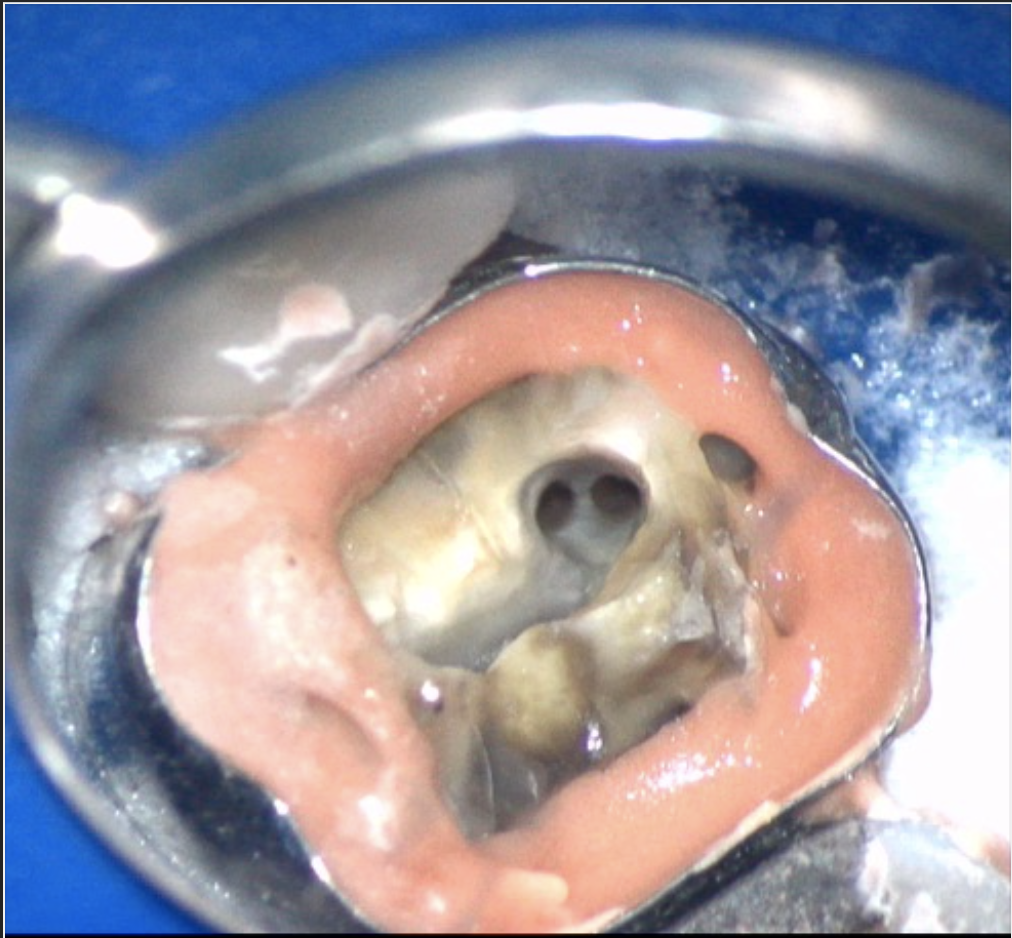

• Management of curved canals, calcified canals, and difficult access cases.

• Advanced use of CBCT and magnification (microscope) for navigation.

• Using bioactive materials (MTA, Biodentine)